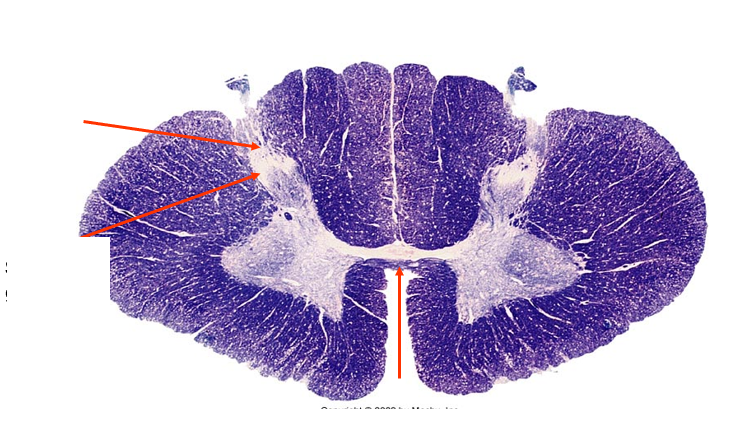

demyelination of fasciculus Gracilis

Tabes Dorsalis